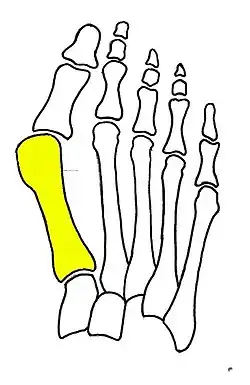

Syndesmosis procedure addresses specifically the two fundamental problems of metatarsus primus varus deformity that gives rise to the bunion deformity. They are leaning and instability of the first metatarsal bone . Syndesmosis procedure uprights the leaning first metatarsal bone with strong binding sutures between it and the second metatarsal bone (Fig. 2) and then also stabilizes it uniquely by creating a fibrous connecting bridge between these two bones (Fig. 3, 4). First metatarsal bone can be readily realigned because by definition of the metatarsus primus varus deformity its first metatarsal is abnormally loose and mobile.